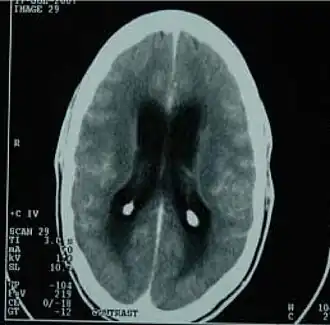

TAC del cerebro mostrando una meningitis tuberculosa.